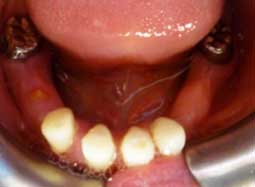

Extraction des dents temporaires, élongation coronaire chirurgicale des secteurs antérieurs supérieur et inférieur (Fig 5) et freinectomie (Fig 6).

La phase prothétique proprement dite comprend :

1- La réalisation de coiffe pédodontique préformée sur les dents de six ans (Fig 7, 8, 9),

2- La réalisation de couronnes en polycarbonate au niveau des secteurs antérieurs (Fig 10),

3- La réalisation d’une prothèse amovible (Fig 11, 12, 13),

4- Un suivi régulier et un contrôle de l’éruption des dents (Fig 14, 15, 16, 17).